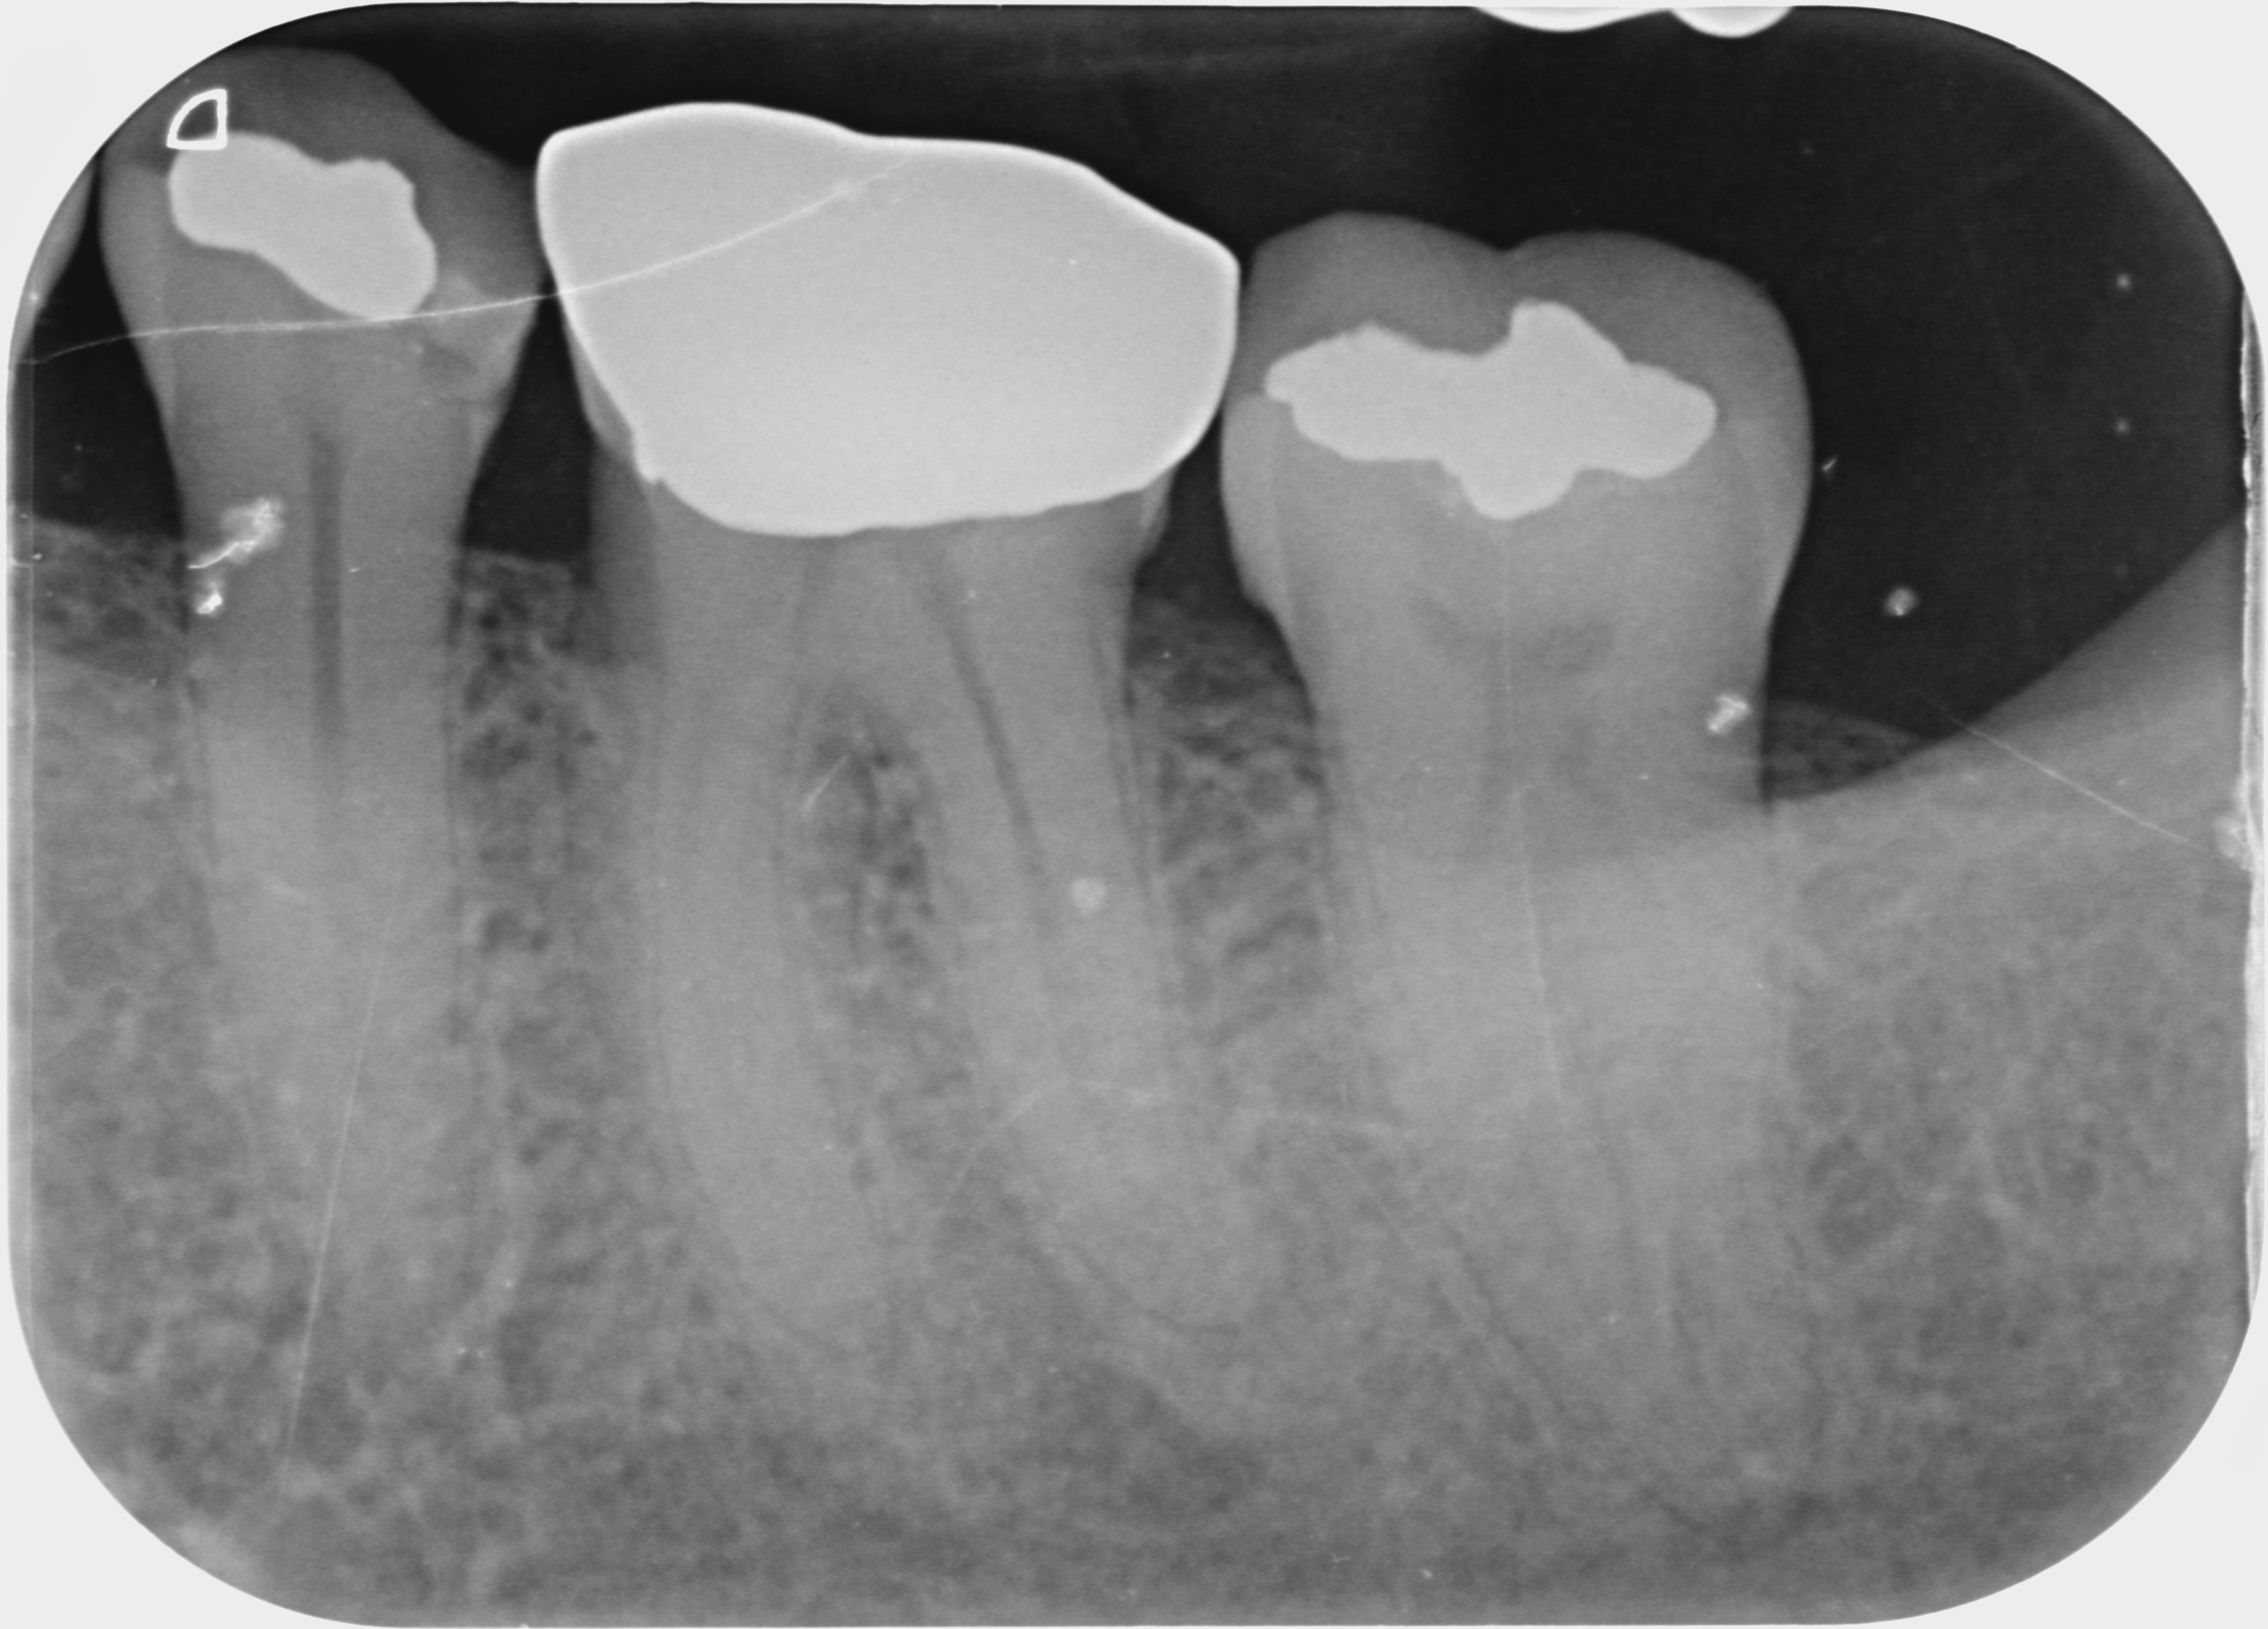

A 72-year-old patient presented to our clinic for whom crown treatment of tooth #37 was planned owing to the patient complaining of recent pain on biting without lingering symptoms. However, the procedure was delayed owing to COVID-19 lockdown orders, and when the patient returned for treatment, he reported that symptoms had escalated to constant aching during the day and night, subsiding after a week. On examination, tooth #37 was tender to percussion and not responsive to cold testing and showed an associated periapical radiolucency on the radiograph (Fig. 1).

Fig. 1. (All images: Dr Brenda Loh)

The patient’s heavy bruxing habits had led to the formation of fractures in the enamel and dentine. Further propagation of the fractures had led to pulpal irritation and bacterial ingress, which caused irreversible pulpitis and ultimately pulp death. The diagnosis was pulp necrosis and symptomatic periapical periodontitis.